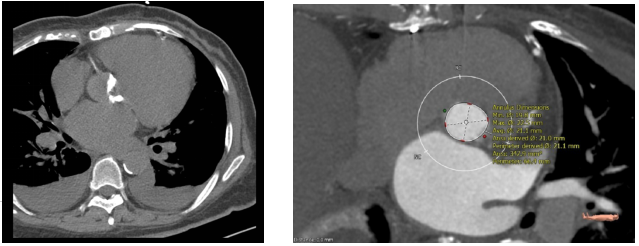

主动脉根部CTA:

主动脉二叶式畸形,瓣膜增厚,存在重度钙化,分布于两个瓣叶游离缘。主动脉瓣环周长折算直径21.1mm

瓣膜选择:根据患者主动脉CTA重建图像,确定患者适用21# J-Valve自膨胀生物瓣膜